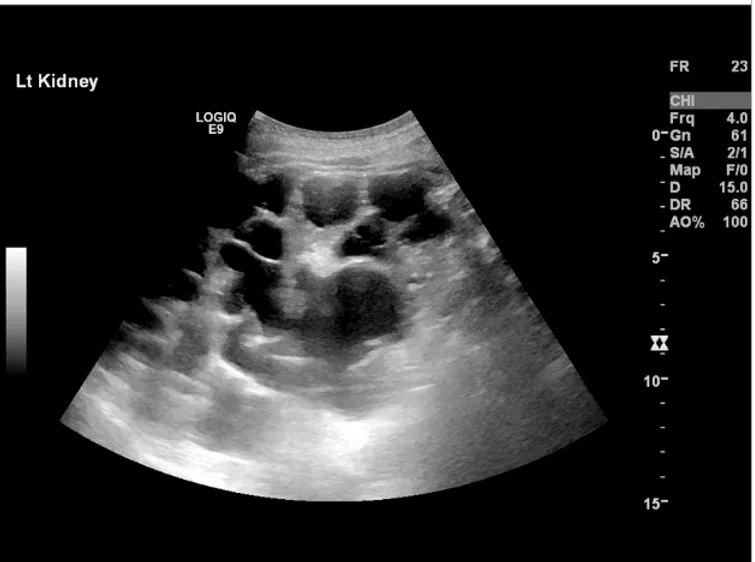

Amiloidose renal: aspectos sobre patogenia, diagnóstico e proteomica

Este vídeo apresenta, de forma didática e baseada em evidências, os principais achados da tese de doutorado sobre amiloidose renal, com foco em proteômica glomerular e ativação do complemento. São discutidos aspectos diagnósticos, implicações fisiopatológicas e correlações clínico-patológicas relevantes para a prática do nefrologista. O conteúdo sintetiza dados inéditos de matriz extracelular glomerular e diferencia perfis entre subtipos de amiloidose. Trata-se de um material aprofundado e acessível, ideal para atualização de especialistas na área.